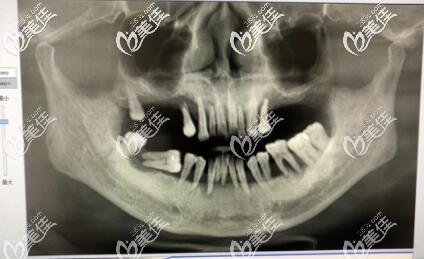

李孟奇院長指出:患有牙周炎是不可以做種植牙的,因為很容易導(dǎo)致種植牙失敗,一定要等牙周炎治療好了,在去醫(yī)院做種植牙。牙周炎病患者常會導(dǎo)致牙齦萎縮,形成牙周袋,使得牙根暴露,牙齒松動,在這樣的牙齒上再加上瓷冠更會增加牙周負擔,加重牙周炎病。如果要做,必須在牙周病控制后再進行。

牙周炎后的義齒修復(fù)必須建立在健康的牙周基礎(chǔ)之上。且必須清除所有與牙周炎有關(guān)的病原刺激,包括菌斑、牙石等,建立起有效的菌斑控制手段,消除或控制牙周袋,防止牙周病再度復(fù)發(fā),否則即使種上再好的種植體,也是徒勞無功。